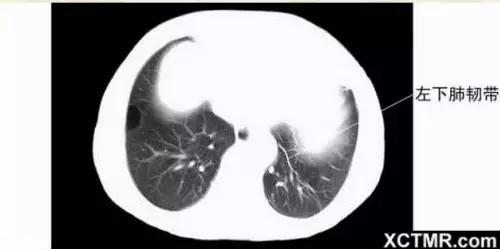

肺段划分